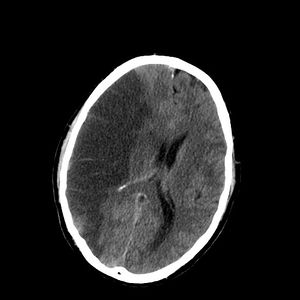

التشخيص

التصوير